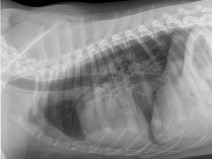

• Après-midi Travaux pratiques de radiographie / TP1 Le Thorax

Le GEIM vous propose une séance de travaux pratiques de radiographies sur le thorax. Tous les aspects sont abordés sous la forme de TP de lecture de radiographies numériques sur station de travail Osirix sur Mac (3 vétérinaires maximum/ordinateur).